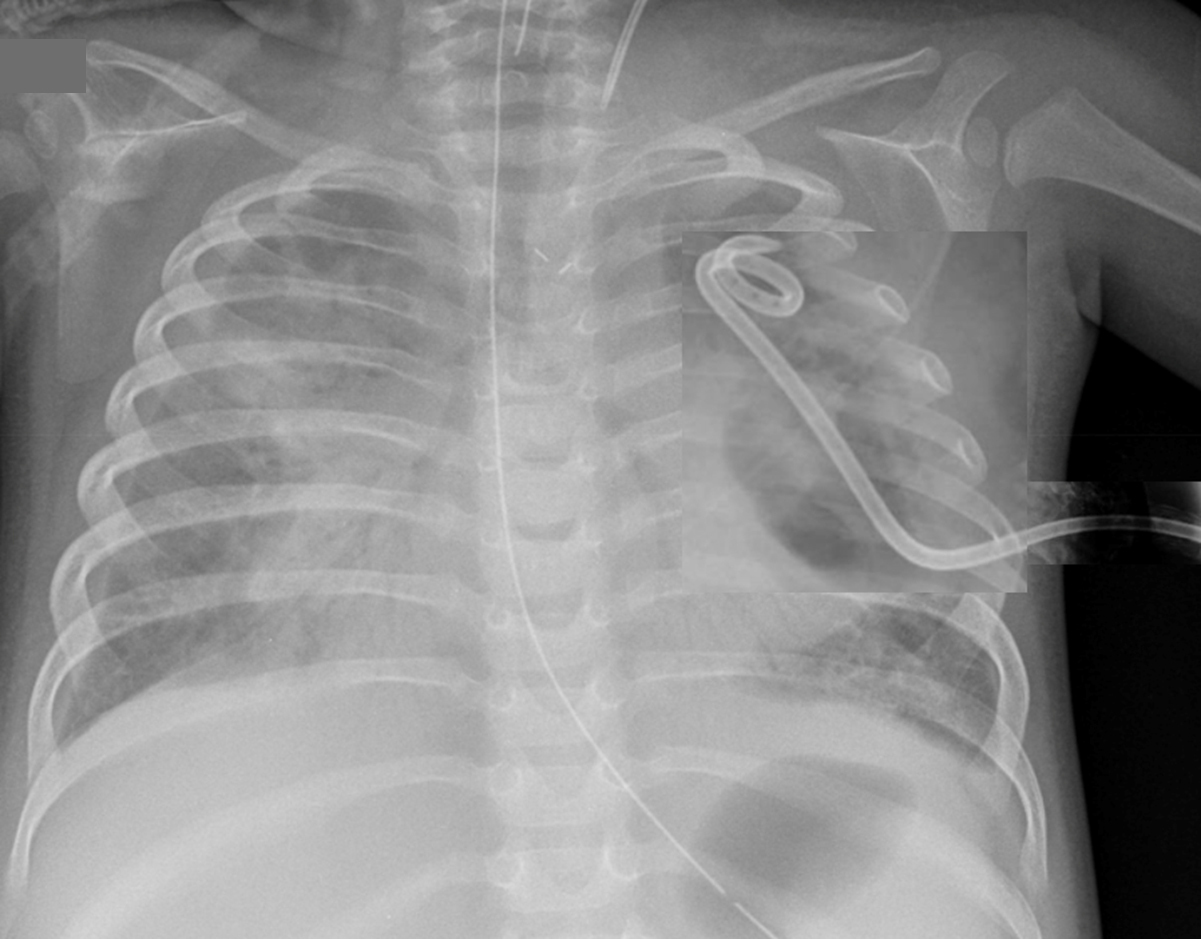

Fréquence respiratoire (FR) = 50/min ; tirage sous-costal sans autre signe de lutte respiratoire ; murmure vésiculaire bilatéral et symétrique avec doute sur des crépitants en base gauche ; saturation en oxygène (SpO2) = 96 % en air ambiant.

Radiographie thoracique indiquée.

Toute toux fébrile n’est pas une pneumopathie. Les signes faisant évoquer une infection respiratoire basse sont la fièvre associée à une polypnée, ou à des signes de lutte respiratoire, ou à une anomalie à l’auscultation pulmonaire. Une radiographie thoracique de face en inspiration est donc indiquée pour confirmation.